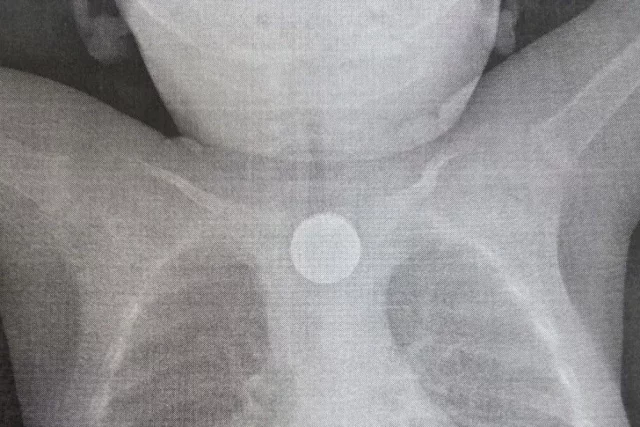

Однако бессонные ночи, постоянный стресс, физическая нагрузка и большая ответственность всё это серьёзно сказалось на здоровье Николая Таракановского. Ему пришлось пройти химиотерапию и лечь на операционный стол.

«После перенесенной болезни понял, что уже не хватает здоровья для работы в реанимации, но уходить из любимой профессии не хотел да и не мог — докторов категорически не хватает», — рассказал Николай Таракановский.